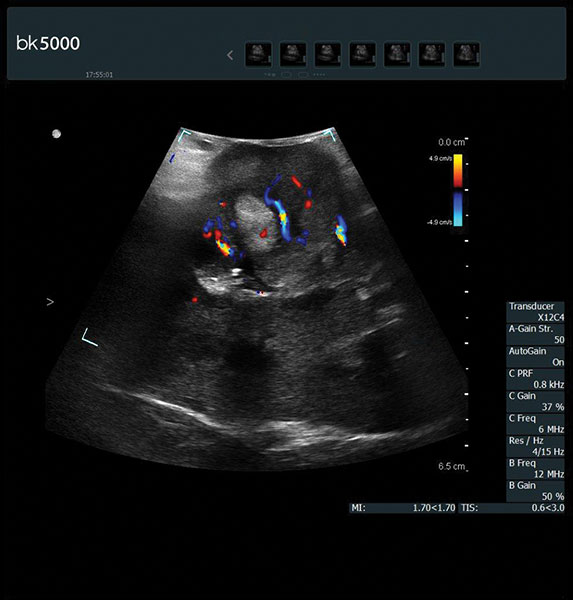

Superb Color Doppler And Unique 3D Visualization

Extremely sensitive color Doppler with superb spatial resolution identifies arterial and venous blood supply to the tumor. This is especially important in procedures where selective clampingis needed. Unsurpassed 3D imaging enables easier identification of key anatomical landmarks and dissection planes.